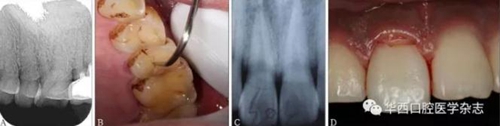

(3)X線片結果具有隱蔽性,需仔細結合臨床檢查進行判斷。如圖3所示,X線片未見折裂線(圖3A),而臨床檢查可見明顯的縱折(圖3B);有時X線片僅顯示1條折裂線(圖3C),而臨床檢查發(fā)現為復雜冠根折(圖3D)。

A:X線片未顯示根折;

B:臨床檢查可見明顯根折;

C:X線片僅顯示1條唇側牙折線,舌側折裂線不清晰;

D:臨床檢查可見右側上頜中切牙出現明顯冠根折。

圖 3 X線片與臨床檢查對比結果